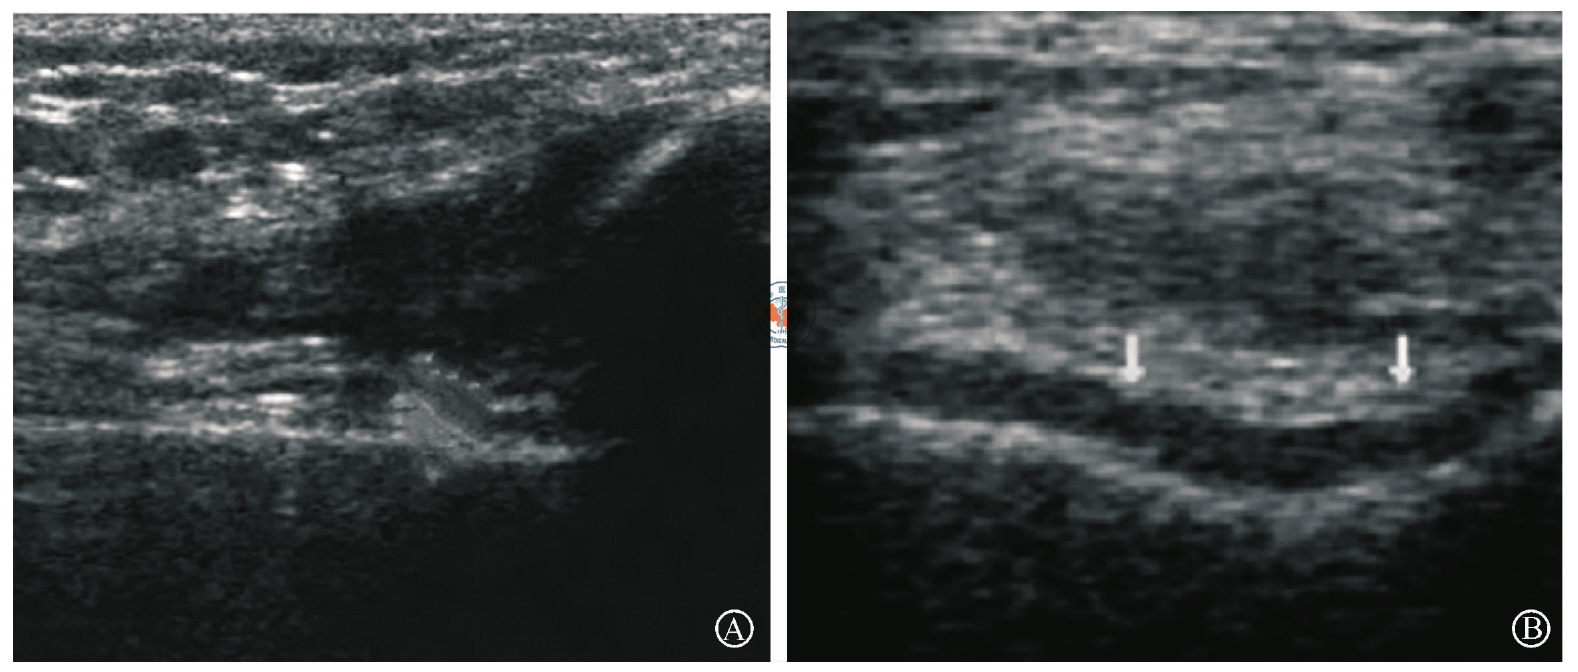

图1 KOA(膝骨关节炎)治疗前后膝关节两侧间隙超声图像。图A为入组时图像,示关节腔内存在大量积液,肌纤维排列紊乱,滑膜增生肥厚,肌腱端增生,腘窝囊肿,关节软骨变薄且毛糙,骨面连续性中断;图B为治疗后6个月图像,示关节腔内积液明显减少,肌纤维排列清晰注:箭头指示滑膜变薄,关节软骨光滑,腘窝囊肿消失,骨面平滑且连续

Figure 1 Ultrasound images of bilateral knee spaces of KOA patient before and after treatment. A is ultrasound image before treatment, showing that there was a large amount of fluid in the joint cavity, muscle fiber arrangement disorder, synovial hyperplasia and hyperplasia, tendon end hyperplasia, popliteal cyst, thin and rough articular cartilage, and continuity of bone surface was interrupted; B is ultrasound image six months after treatment, showing that the fluid accumulation in the joint cavity significantly reduced, the muscle fibers clearly arranged Note: the arrow indicated that the synovial membrane was thinner, the articular cartilage was smooth, the popliteal cyst disappeared, and the bone surface was smooth and continuous